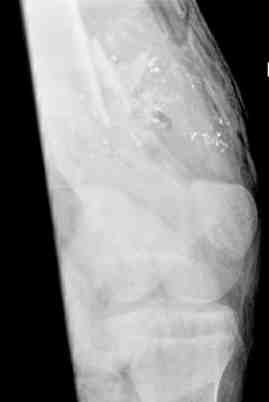

Выше приведены рентгенограммы 13-летнего подростка, страдающего от огнестрельного многооскольчатого перелома дистальной трети бедра. AO наружный фиксатор наложенный в день травмы не дал приемлемой редукции. Через три недели после перелома аппарат Илизарова был наложен без попытки одномоментной репозиции на операционном столе. There are X-Rays of a thirteen year old boy with a comminuted distal femur fracture secondary to a gunshot wound, initially treated with an AO external fixator. The alignment was unacceptable and an Ilizarov external fixator was applied three weeks after the injury. No attempt of definitive reduction was made during the surgery.

Гексаподная приставки наложена на 10 дней и приемлемая редукция была получена. The Hexapod set was applied for ten days and acceptable reduction was received.

По окончанию редукции Гексаподный сет был снят и дальнейшее ведение больного проходило в стандартном режиме аппарата Илизарова. Хороший анатомо-функциональный результат был получен. When reduction was finished, the Hexapod set was removed and further management has been continued by standard Ilizarov regime. Good anatomic and functional results were achieved.